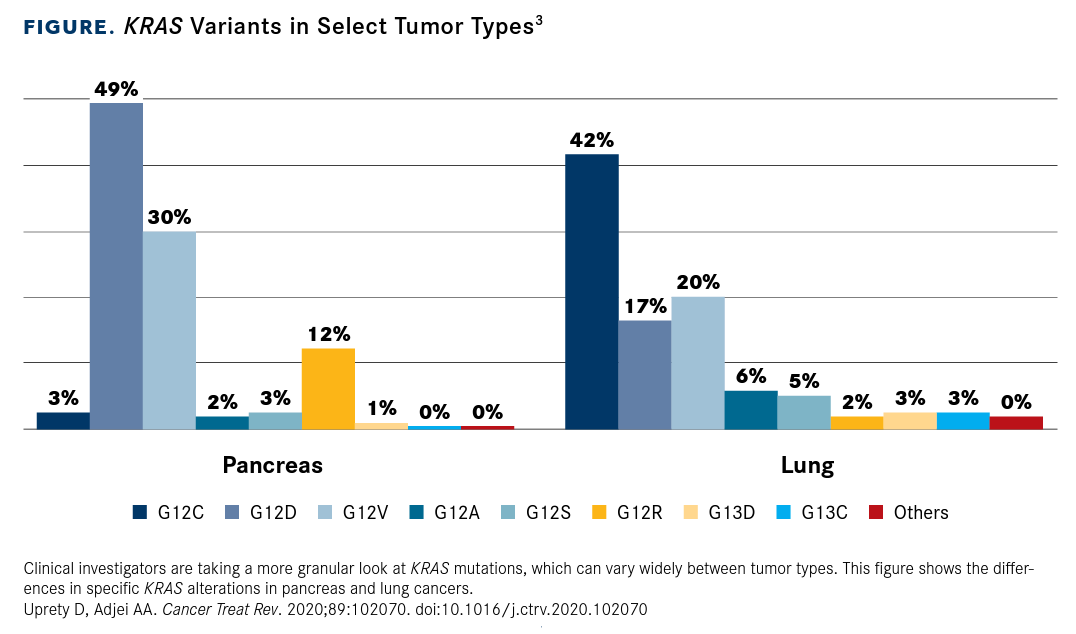

KRAS mutations are common in other cancer types as well as NSCLC, but there is substantial variation in the position and type of mutation (FIGURE3). In pancreatic ductal adenocarcinoma cases, for example, the vast majority of which harbor KRAS mutations, the most common KRAS alteration is the G12D substitution.8,10

FIGURE. KRAS Variants in Select Tumor Types3

The specific substitutions observed at each codon even vary across different cancer types. In NSCLC, KRAS G12C mutations (with a glycine-to-cysteine substitution) are the most common, whereas in pancreatic cancer and CRC, the G12D (glycine to aspartate) substitution is more prevalent. CRC is notable for the diversity of KRAS mutations associated with it; mutations at K117 and A146, for example, are rare overall but are found with a significant frequency in CRC.18